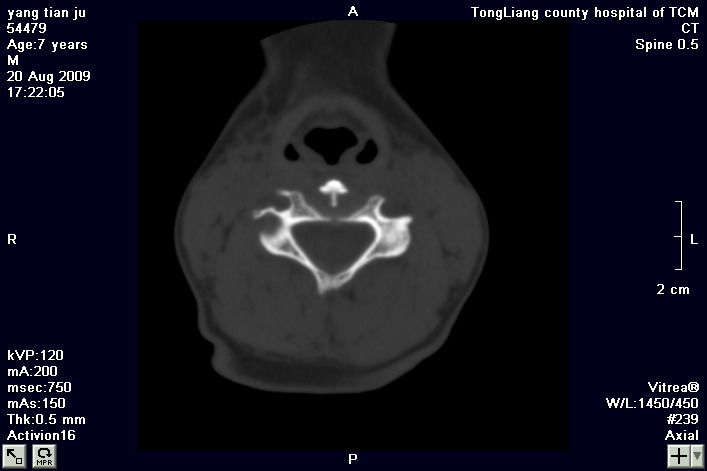

标题: PED2853:颈3/4椎间盘内高密度钙化灶,请各位会诊. [打印本页]

标题: PED2853:颈3/4椎间盘内高密度钙化灶,请各位会诊.

患儿,7岁,颈部疼痛3天,颈部活动受限.

本例应该是典型的儿童钙化性椎间盘病。

儿童钙化性椎间盘病发病年龄多在5~12岁,男女比例相当,大多数患儿发病主要表现为颈部疼痛,伴活动受限。少数有吞咽不适或肢体瘫痪。有一部分患儿无症状,是在其它检查时发现。病因尚不完全明了,可能的有:1、感染。2外伤。

儿童颈椎椎间盘钙化系一良性自限性疾病,可见于颈、胸、腰椎,以颈椎为多发,腰椎少见,多为单发。钙化位于髓核,也可累及软骨板和纤维环引起钙化主要发生于c 4~7  的髓核位于椎间隙正中或偏后,少数向前疝出,以后部多见,呈梭状、盘状、团块状或半环状;(2)颈椎生理曲度变直,椎间隙正常或增宽;(3)相邻椎体可变扁,局部凹陷变形,椎体前下缘鸟嘴状增生,或呈钳口状改变,椎前软组织增厚及环枢椎半脱位;(4)ct可清晰显示椎间盘髓核 位置的钙化灶及经破裂的纤维环向椎管内突出。(5)mri,钙化在t1及t2加权像上均呈低信号,并可见脊髓组织内异常信号。